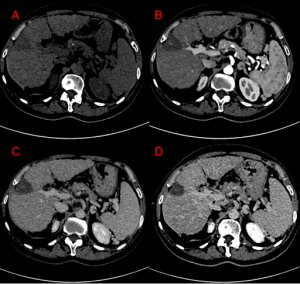

Sono stati inclusi i pazienti le cui immagini fossero acquisite mediante protocollo TC con fase pre-contrastografica, fase arteriosa, fase venosa acquisita TBDE (Twin-Beam Dual Energy) e in fase tardiva (FIGURA 1).

FIGURA 1. Esempio di alcune scansioni TC sul medesimo piano del protocollo adoperato per lo studio: pre-contrastografiche (A), in fase arteriosa (B), venosa (C) e tardiva (D). È inoltre possibile osservare ll'ipodensità al passaggio epatico S8-in esiti di trattamento post-ablativo.